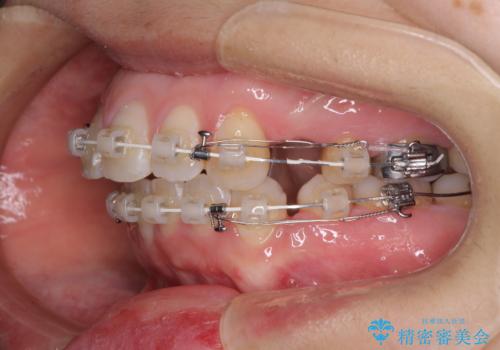

- 矯正装置

- 審美装置

- 口元の閉じにくさと、前歯のでこぼこの歯並びを気にして来院された患者様です。

口元を積極的に引っ込めるために、上下左右の小臼歯計4本を抜歯することとしました。

セオリーでは第一小臼歯を抜歯しますが、上下右側は第二小臼歯に銀歯が装着されているため、第二小臼歯を抜歯することとしました。

上下正中を左右対称に揃えるため、アンカースクリューや補助装置を使用しながら口元を下げていくこととしました。